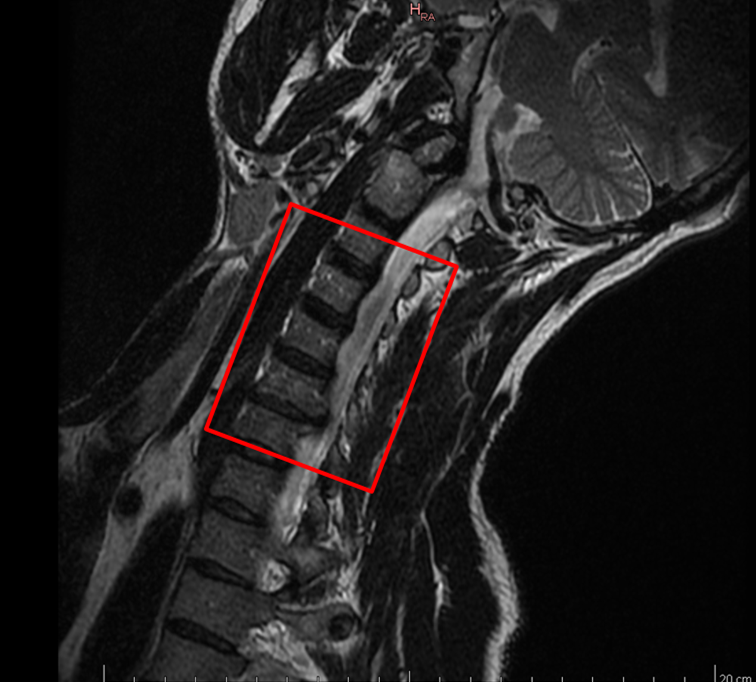

Mein Bandscheibenvorfall feiert nun in 8 Tagen seinen dritten Geburtstag.